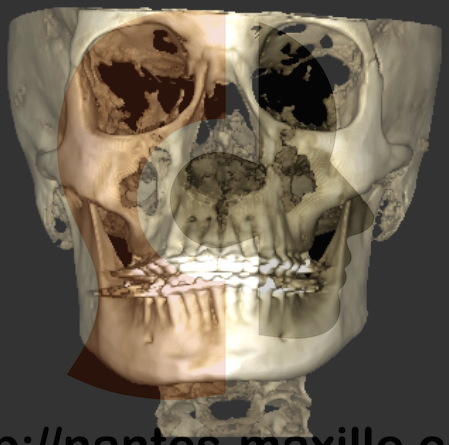

dans une assymétrie verticale, il est possible d’abaisser la Gauche et remonter la droite la mandibule. Il reste ensuite à horizontaliser le maxillaire.

Hypercondylie droite opérée par une condylectomie par un abord externe, associée à un abaissement de l’angle mandibulaire Gche, remontée de l’angle mandibulaire droit, et une horizontalisation du maxillaire